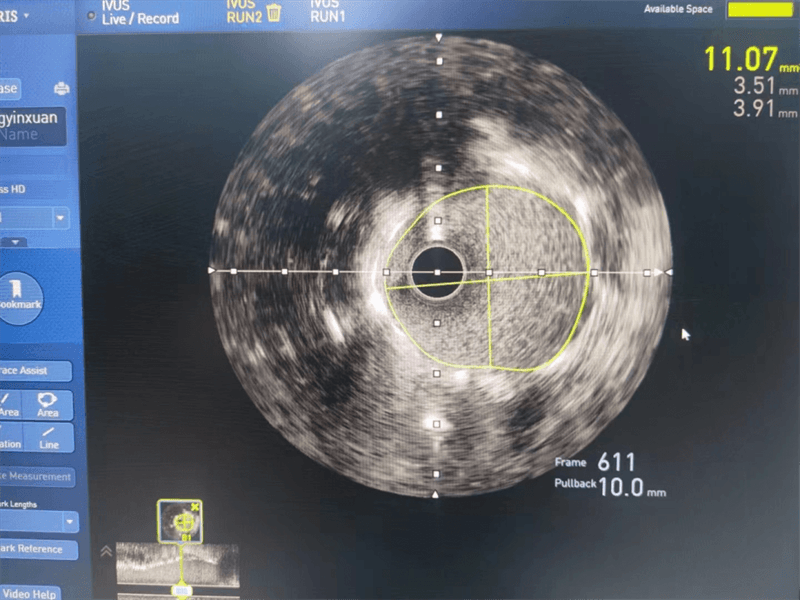

與患者家屬溝通后,其女兒猶豫不決、憂心忡忡,經(jīng)過(guò)崔主任認(rèn)真分析病情、充分溝通,征得患者及家屬同意后,為安全、精準(zhǔn)處理病變,選擇進(jìn)行血管內(nèi)超聲檢查,經(jīng)血管內(nèi)超聲檢查提示左主干至前降支近段纖維斑塊,球囊擴(kuò)張后面積3.97mm2,斑塊負(fù)荷70%,回旋支近段中度狹窄,斑塊負(fù)荷較輕。

我們結(jié)合患者病變特點(diǎn),對(duì)回旋支支架內(nèi)閉塞病變處藥物球囊治療,左主干病變植入1枚支架,術(shù)后,造影顯示左主干病變處支架植入狀態(tài)良好,血管內(nèi)超聲顯示支架貼壁良好,患者血壓、心率穩(wěn)定,癥狀完全緩解,并安全返回重癥監(jiān)護(hù)室進(jìn)一步治療,術(shù)后張大伯無(wú)明顯不適,生命體征穩(wěn)定,病情明顯好轉(zhuǎn)。